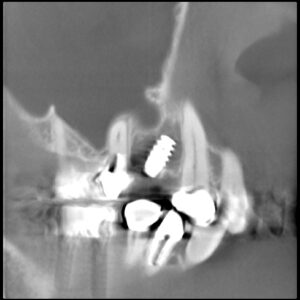

50女性 3DXCT ノーベルアクティブインプラント オペ時間18分